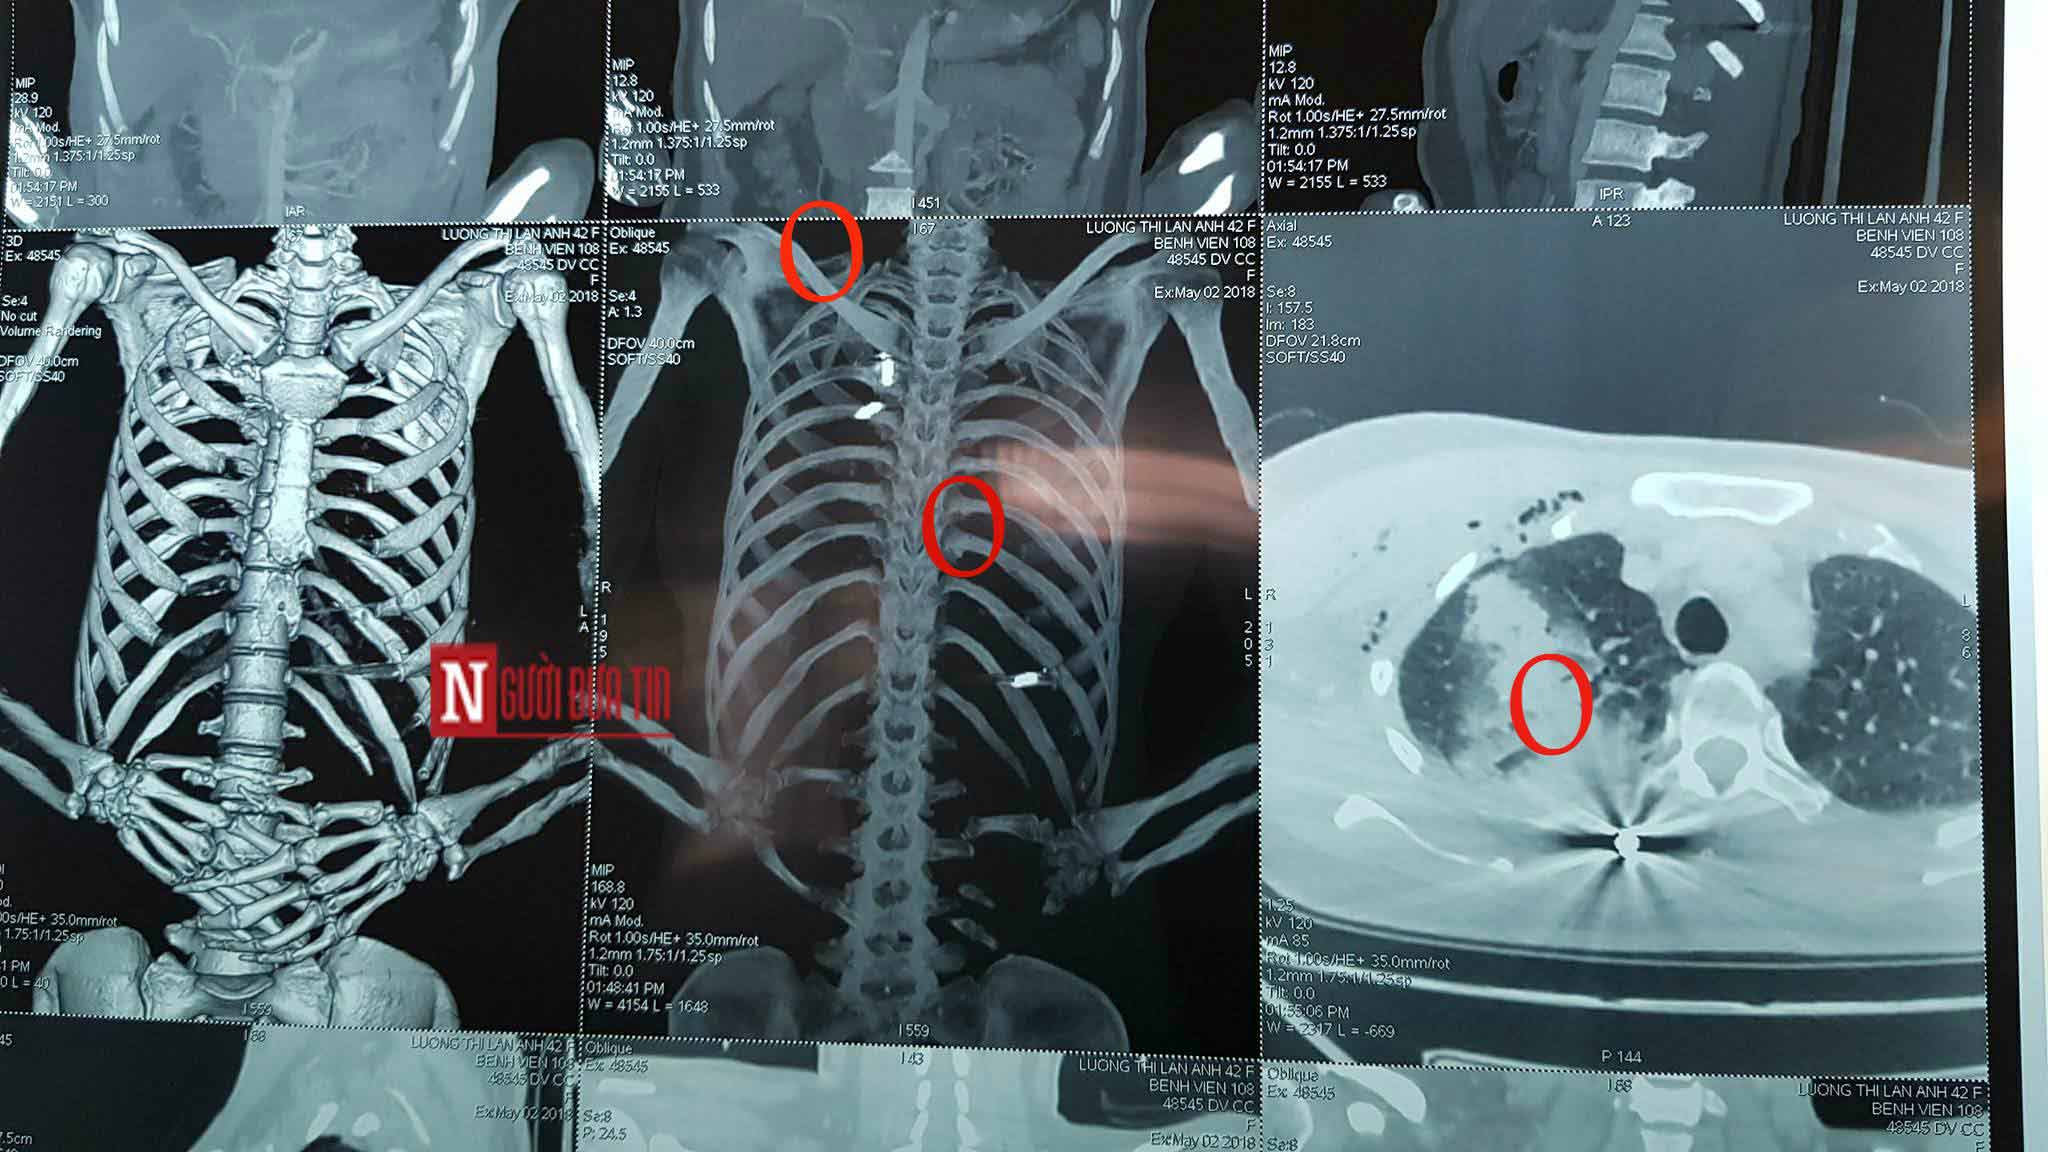

Những viên đạn găm trong người chị A. (khoanh tròn đỏ). |

Bà Bùi Ngọc Huệ, điều dưỡng trưởng của khoa Phẫu thuật lồng ngực, cho biết: “Bệnh nhân Anh được đưa vào đây trong tình trạng hoàn toàn tỉnh táo, có thể giao tiếp được. Nhưng trên người phía sau tai, phần cổ và trước ngực có nhiều vết thương hình tròn nhỏ do vết đạn bắn vào người. Thể hiện trên phim chụp thì cho thấy có nhiều vết đạn găm vào trong người của chị Anh.

Khi được đưa vào đây, nạn nhân bị tràn dịch màng phổi và chảy máu màng phổi do có một viên đạn bắn xuyên vào phổi. Hiện tại, chúng tôi đang hoàn tất các xét nghiệm để tiến hành phẫu thuật lấy viên đạn ra khỏi người chị Anh”.